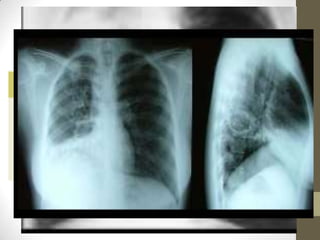

Cavidad en pulmón derecho

Rx que muestra cavidades con niveles

hidroareos e infiltración en el lóbulo